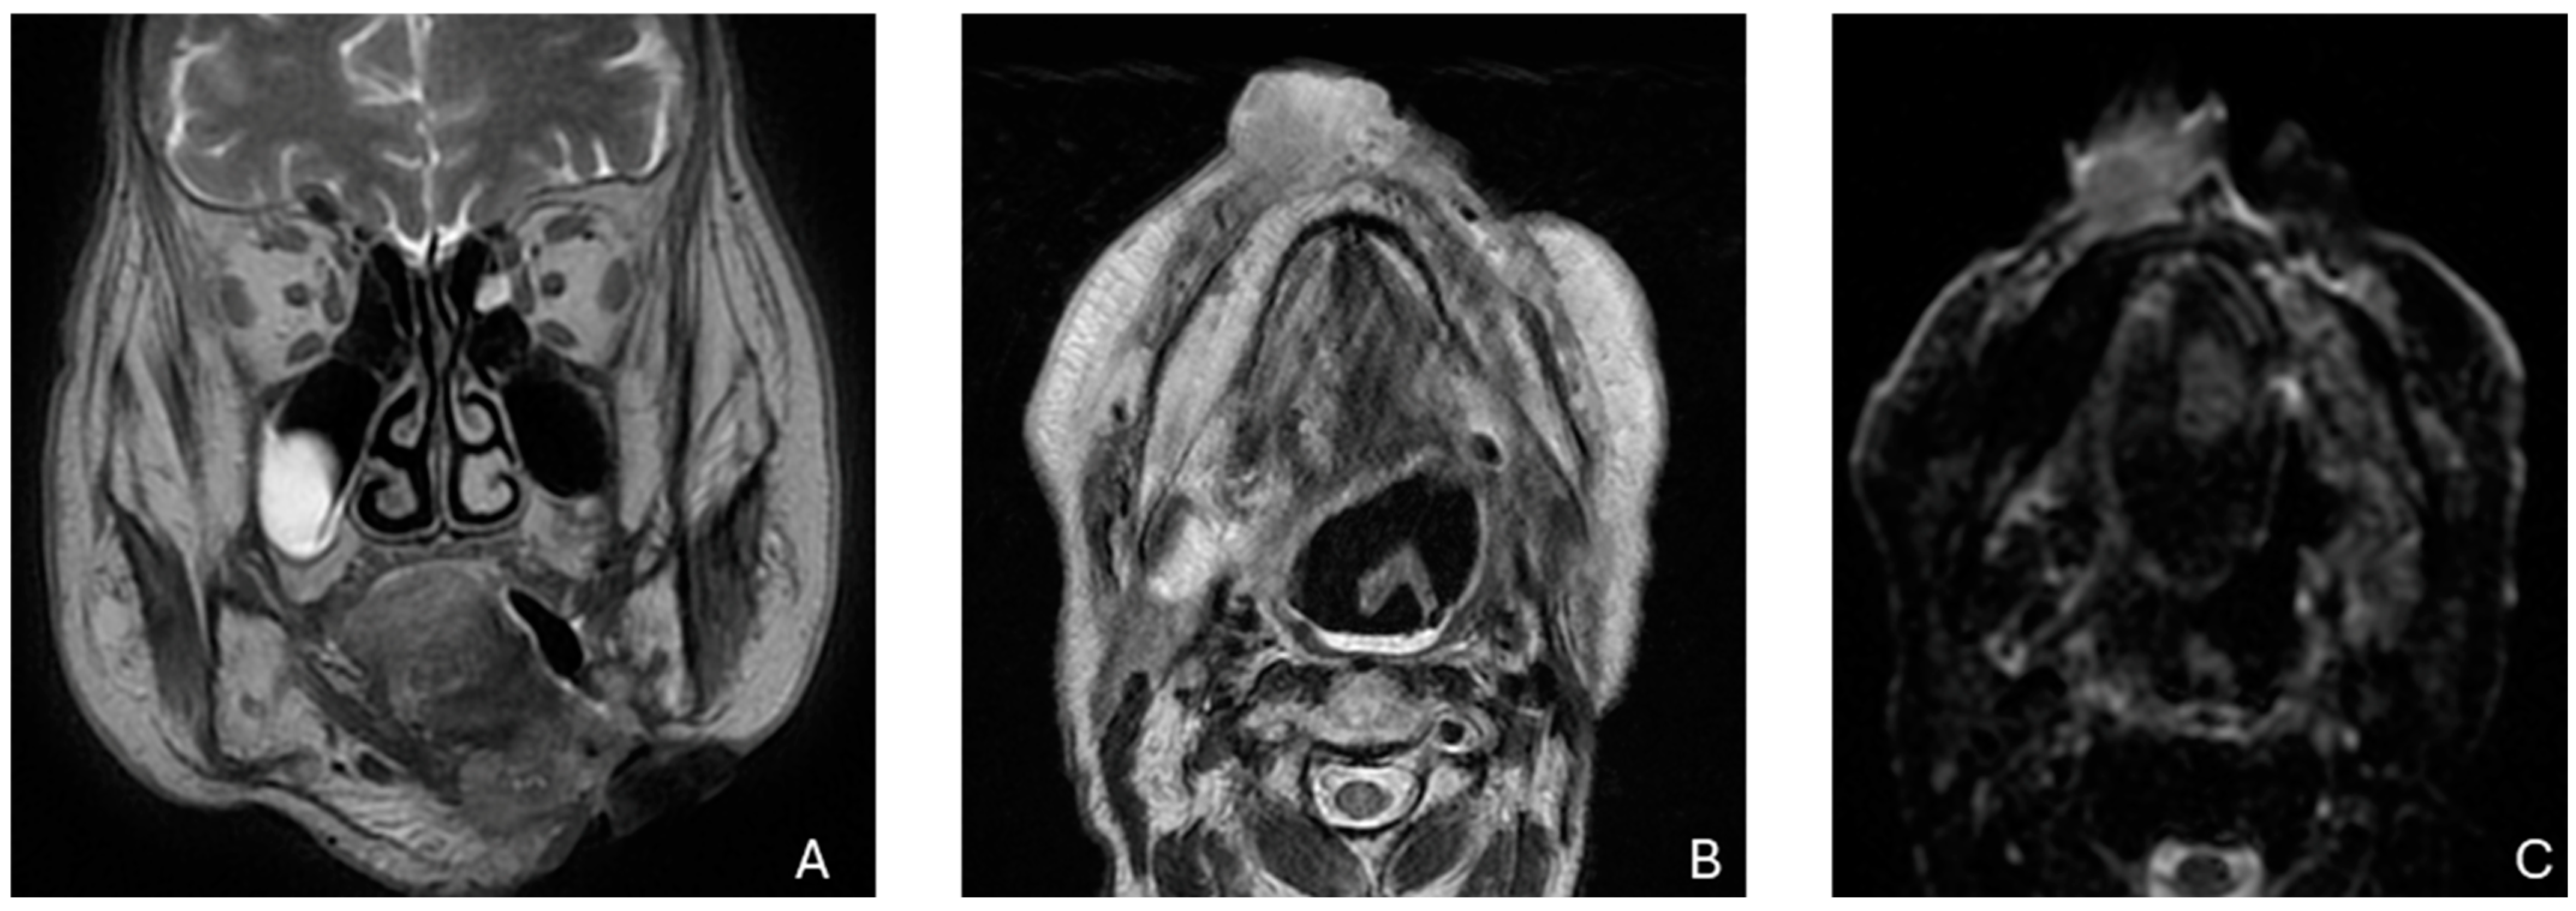

- Kim, S.Y.; Beer, M.; Tshering Vogel, D.W. Imaging in Head and Neck Cancers: Update for Non-Radiologist. Oral. Oncol. 2021, 120, 105434. [Google Scholar] [CrossRef] [PubMed]